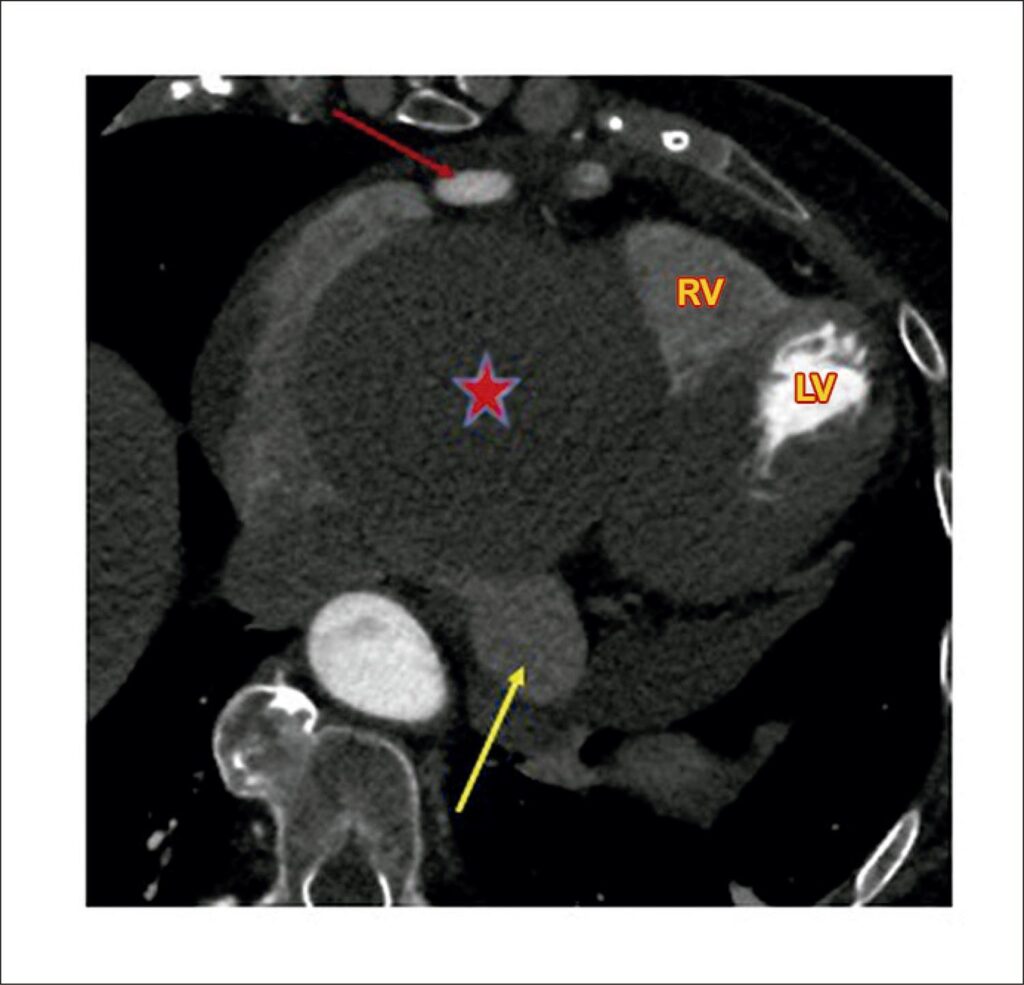

Giant Right Coronary Artery Aneurysm with Arteriovenous Fistula

Coronary artery aneurysm (CAA) is defined as a dilation that exceeds the normal diameter of the adjacent artery or the diameter of the patient’s largest coronary artery by 1.5 times. Some authors consider a giant coronary aneurysm when the diameter is > 20 mm, whereas the American Heart Association defines giant aneurysms as those > 8 mm. Giant CAA is a rare pathology with an approximate incidence of 0.02%. We report a case of giant right coronary artery aneurysm with fistula to the coronary sinus, appearing as a giant “mass”.